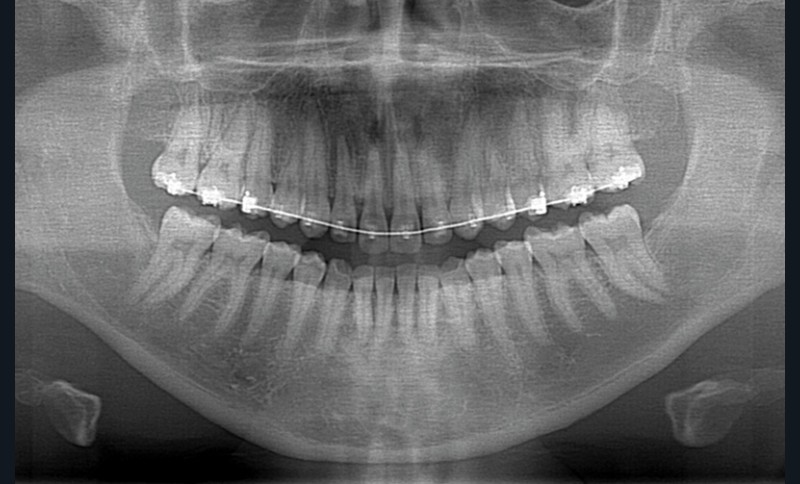

La patiente, outre une allergie au pollen, ne présente pas d’antécédents. L’examen parodontal initial révèle une enveloppe parodontale saine avec une gencive en « peau d’orange » et une pigmentation ethnique ; l’examen radio-clinique du secteur 14-24 met en évidence une hauteur de plus de 3 mm de gencive attachée, des poches vestibulaires et interproximales de 3 à 5 mm sans atteinte osseuse (fig. 3) ni migration de l’attache épithélio-conjonctive.